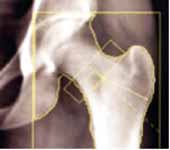

"Zlatni standard" i jedina pouzdana metoda o tkrivanja osteoporoze je koštana denzitometrija-mjerenje koštane gustoće (koštane mase). Najsuvremenija tehnika zasniva se na "metodi dexa" koja koristi rendgenske zrake dviju različitih energija, a pokazuje gustoću minerala u kosti izračunatu u gramima na četvorni centimetar. Metoda je potpuno bezbolna, nije potrebna nikakva posebna priprema, normalno možete jesti i piti, te popiti terapiju koju inače uzimate, prije pregleda. Takodjer, možete se obući kako želite ali bez metalnih dijelova, dugmadi, kopči… Pretraga je jednostavna i brza, traje 5-10 minuta. Doza zračenja primljena pri denzitometriji tako je mala da se ni osobe koje rade s uređajem ne štite posebno i iznosi 1-3 mRem, što odgovara dozi zračenja koja se primi tijekom leta avionom u trajanju 3-9 sati ili na površini Zemlje od kozmičkog zračenja u trajanju od 3-9 dana. Za usporedbu, pri rengenskom snimanju pluća prosječna doza zračenja je 300 mRema. Prosječna doza zračenja na površini Zemlje koju ljudi godišnje prime iznosi oko 400 mRema

Rentgensko snimanje kostiju nesigurna je i neprecizna metoda. Greška u procjeni koštane mase je 30-50%. Na osnovu ove pretrage pouzdano se postavlja dijagnoza osteoporoze tek kod gubitka koštane mase većeg od 30-40%. Na osnovu gustoće kosti (mjeriti će se lumbalna kralješnica i bedrena kost / kuk) ljekar će moći procijeniti u kakvom su stanju Vaše kosti (tj. radi li se o osteoporozi ili ne) i preporučiti Vam daljnje postupke, odnosno najbolju terapiju za Vas.